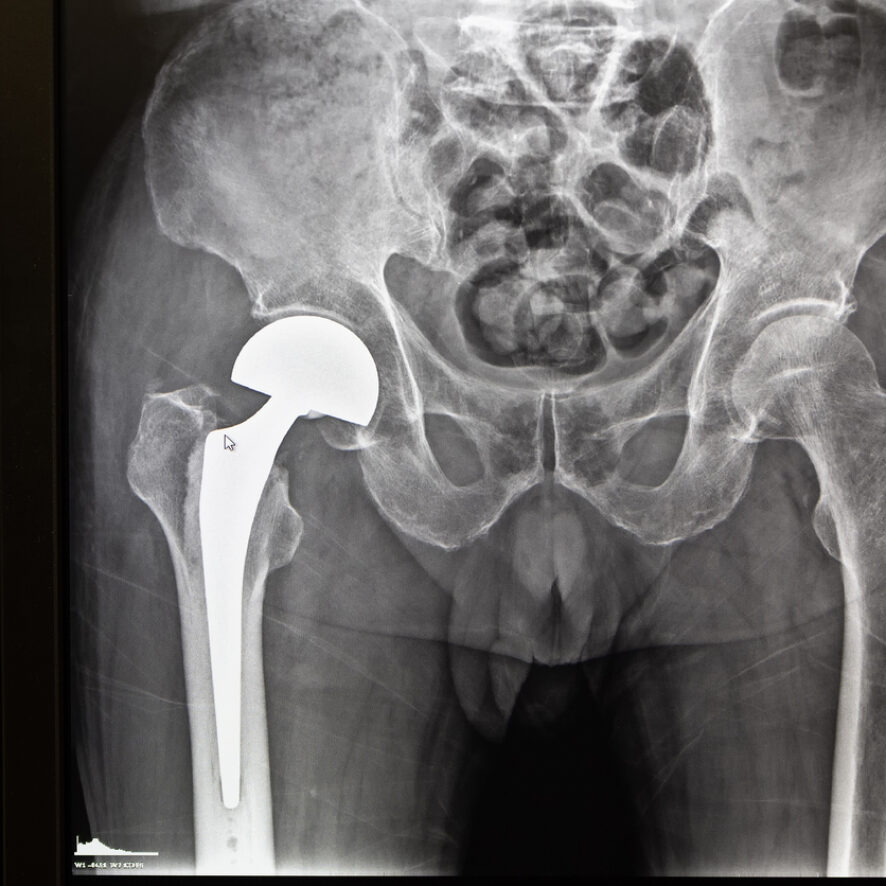

L’essentiel de la pathologie articulaire de l’articulation coxo-fémorale concerne l’usure articulaire. Si le traitement conservateur est impératif au début, l’enraidissement articulaire et les douleurs peuvent réduire considérablement l’autonomie fonctionnelle et la marche. La mise en place d’une prothèse articulaire s’avère alors nécessaire et incontournable.

Le geste chirurgical est simple et permet de retrouver très rapidement une liberté complète et indolente.